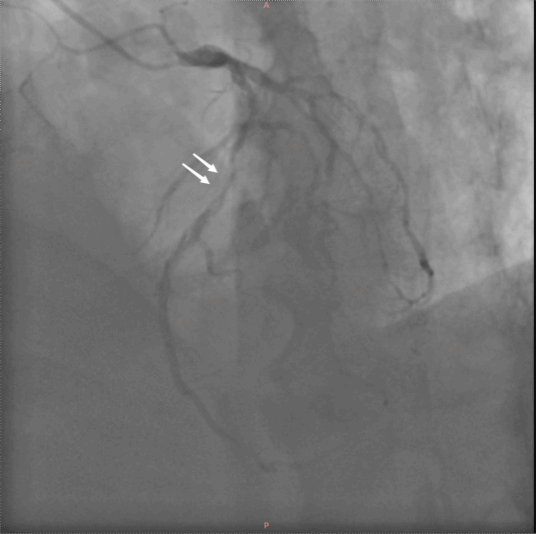

两个月前,老王心梗发作,冠脉造影发现,原先前降支的支架内出现了严重狭窄。

左图:术前冠脉造影(白色箭头指示前降支支架内严重狭窄)